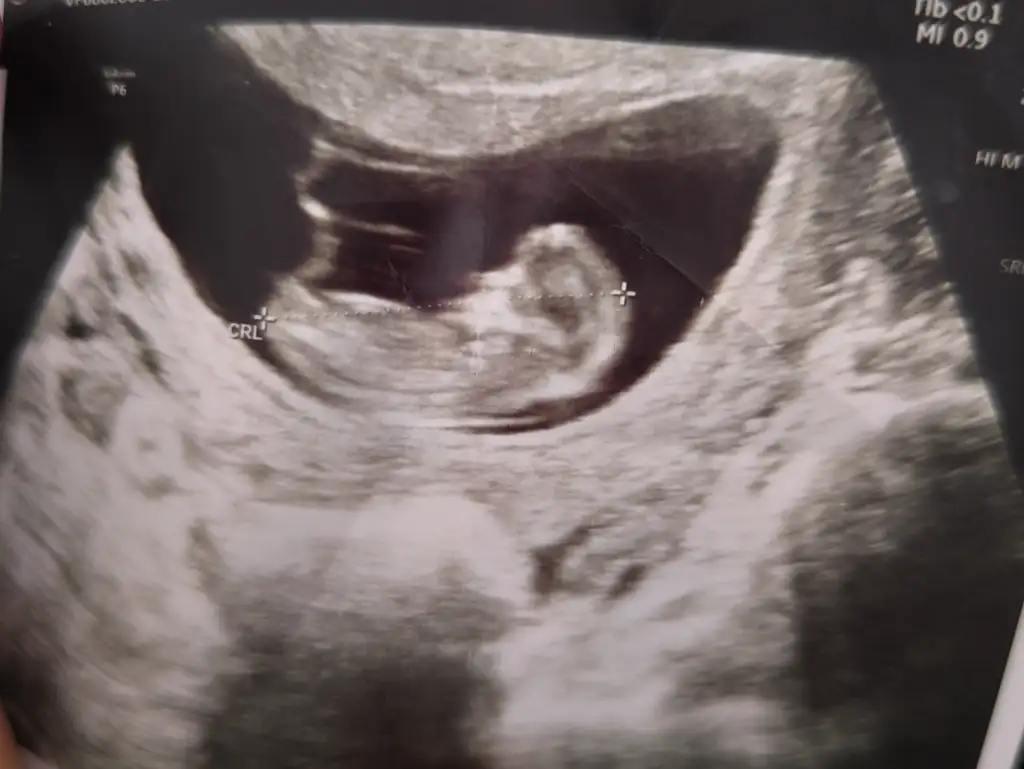

7 haftalık karından bana da bakar mısınız.İlk bebeğim bunun aynısı şekil konum olarak